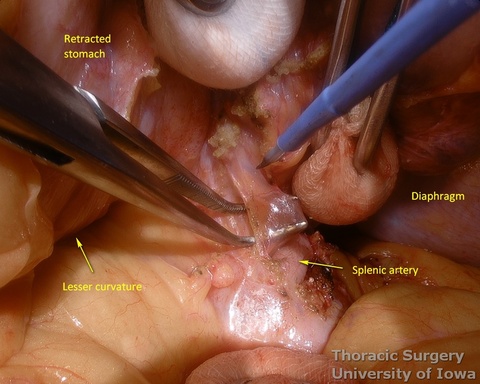

- Peritoneum is incised, protecting the splenic artery and pancreas. 1-2 mm posterior gastric artery, originating from the proximal splenic artery fs present (in half of individuals) and is divided.

- Once the stomach is mobilized and reflected anteriorly, the left gastric vascular pedicle is identified and dissected close to the origin for adequate lymphadenectomy. Care is taken to not injure splenic artery and pancreas.